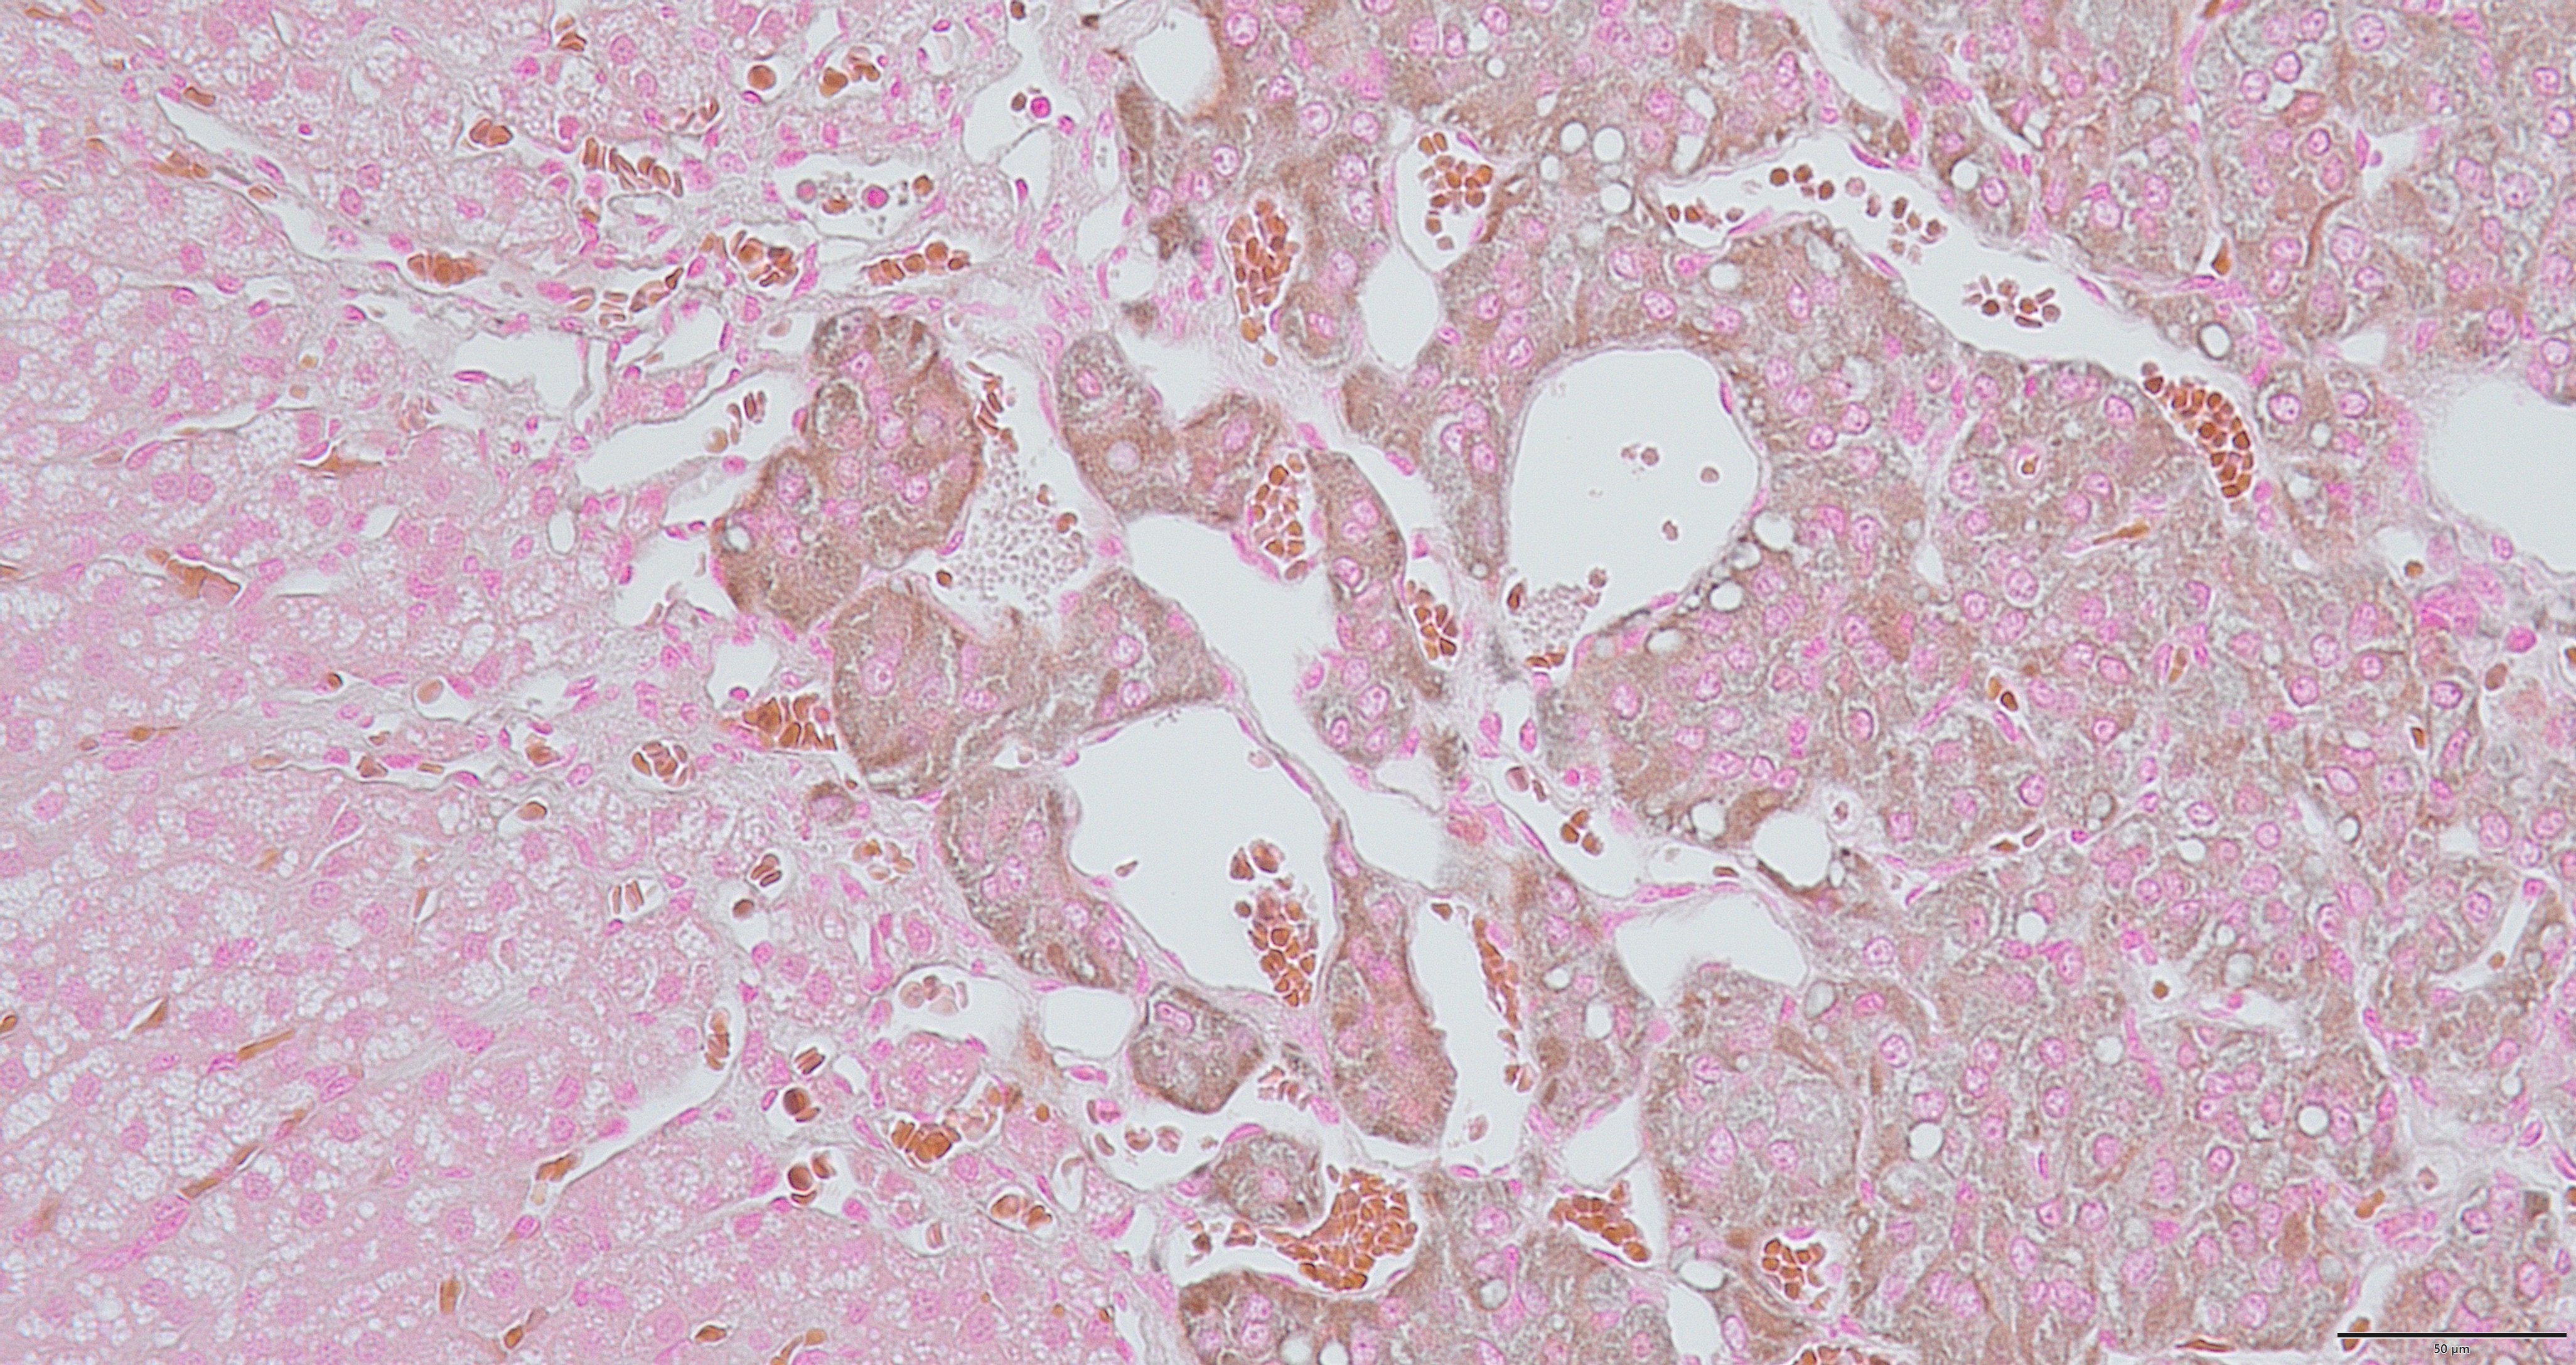

グリメリウス染色は、神経内分泌細胞の検出に特化した銀染色法の一種です。

膵臓や消化管などに存在する「銀親和性細胞(Argyrophilic cells)」 を選択的に染色することで、病理診断における重要な情報を提供します。

- 神経内分泌細胞が持つ還元性物質により、銀イオンが還元されて黒褐色に染まります。

- 明瞭なコントラストが得られ、組織内での細胞の位置や形態が把握しやすくなります。

イヌ,副腎,×40 イヌ,副腎,×400